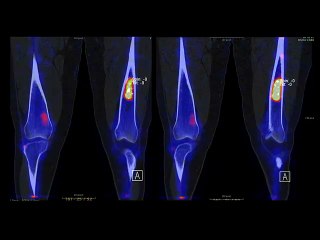

Mystérieuses lésions osseuses phalangiennes…

C.